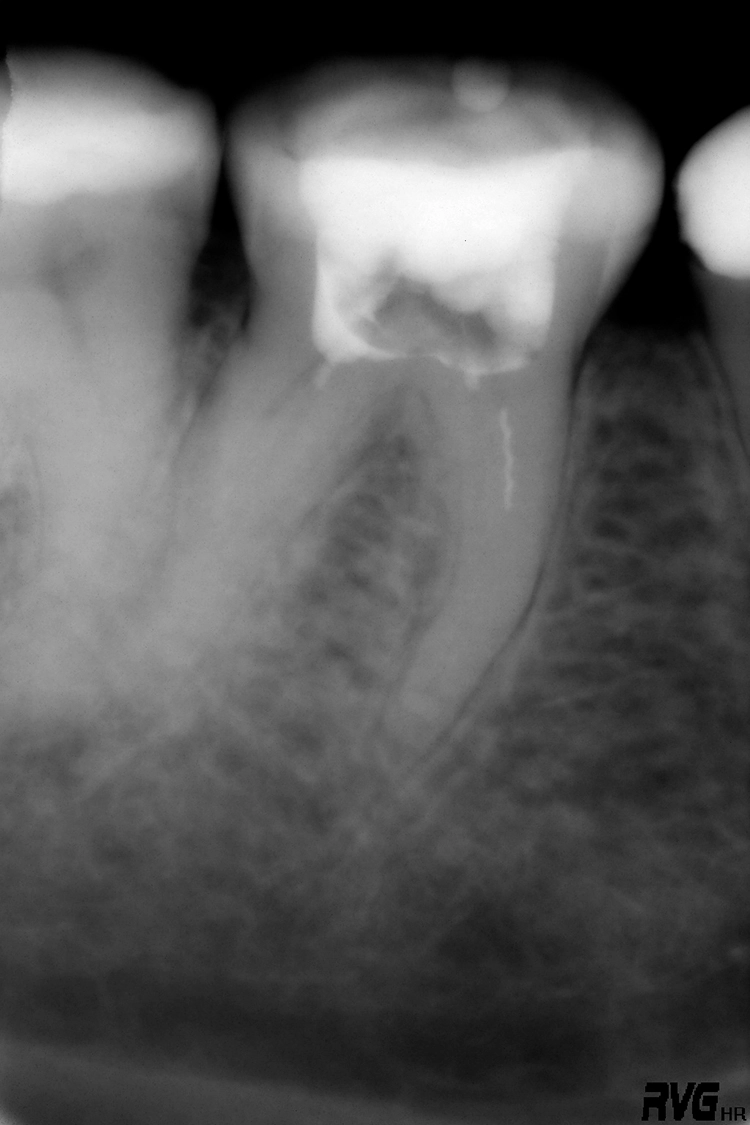

Die Schwierigkeit der mechanischen Ausformung eines Wurzelkanals steigt mit zunehmendem Krümmungswinkel und abnehmendem Krümmungsradius an (Abb. 1). Eine koronale Lokalisierung der Krümmung erhöht die Wahrscheinlichkeit einer Instrumentenfraktur im Vergleich zu einer Krümmung des Wurzelkanals im mittleren oder apikalen Wurzeldrittel [2] (Abb. 2).

Deutlicher zeitlicher Mehraufwand liegt häufig in prozessualen Fehlern, wie bspw. übermäßigem Zahnhartsubstanzabtrag, begründet. Dieser kann zu Kanalverlagerungen und -perforationen führen (Abb. 3a und b), die ein erhöhtes Risiko für anschließende Wurzellängsfrakturen sowie den Verlust des Zahnes darstellen können [12].